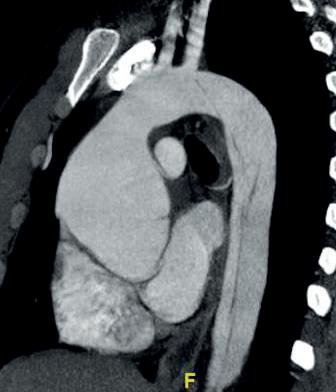

In contrast to CEA, the treatment of abdominal aortic aneurysms (AAAs) and performance of randomized trials do not occur with routine vigor. Performance of open vs. endovascular clinical trials have only occurred in public healthcare systems, both in the U.K. and the U.S. Just look at the results of the EVAR 1 (United Kingdom endovascular aneurysm repair 1) and DREAM (Dutch randomized endovascular aneurysm management) trials to assess quality of AAA repair in the VA. In the EVAR 1 trial, the 30-day operative mortality was 1.8% in the endovascular and 4.3% in the open repair groups. In the DREAM trial, the operative mortality rate was 4.6% in the open repair group and 1.2% for endovascular repair.9,10 With results similar to the other trials, operative mortality was lower with endovascular repair at 30 days compared to open repair but the mortality rate of veterans was markedly less in the endovascular group at 0.5%. A 3% reduction in open mortality was noted compared with other trials.11 The OVER (Open versus endovascular repair) trial is an example of research and clinical outcomes for veterans with AAAs to acknowledge the quality present within the VA system. The VA vascular surgery community can be proud of the outcomes achieved in a challenging population. Direct comparison to the community in clinical trials and real-world data suggest veterans receive care that meets or exceeds community standards (see footnotes at vsweb.org/TBD).